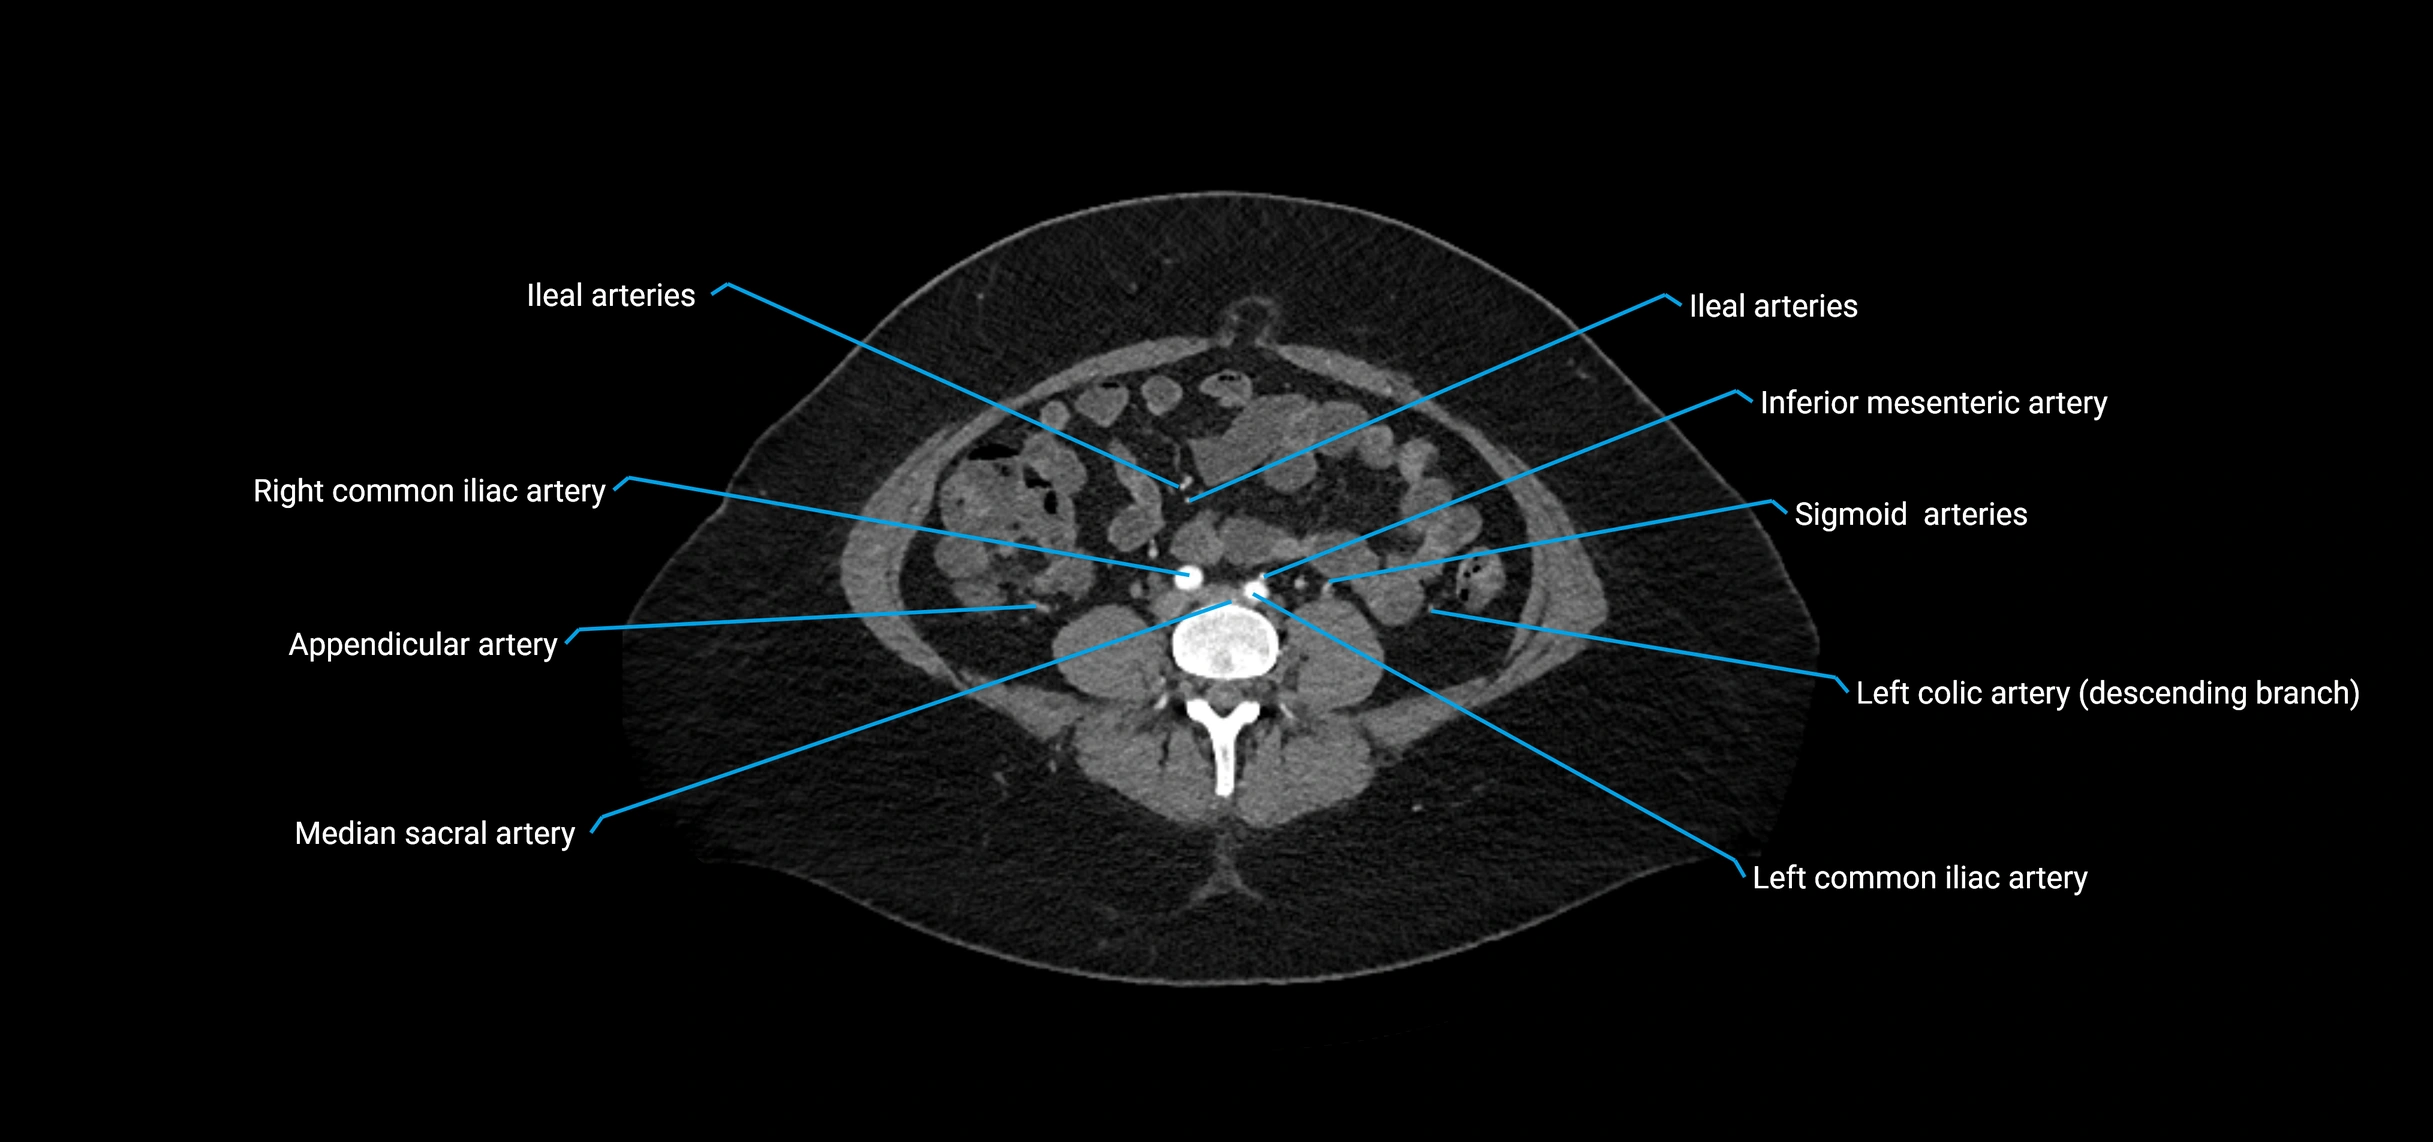

CT images

image

Contrast-enhanced CT (CTA):

• Gold standard for abdominal aortic imaging

• Provides excellent detail of lumen, wall, aneurysm, thrombus, and branch vessels

• Multiplanar and 3D reconstructions help in aneurysm measurement, stent graft planning, and dissection evaluation